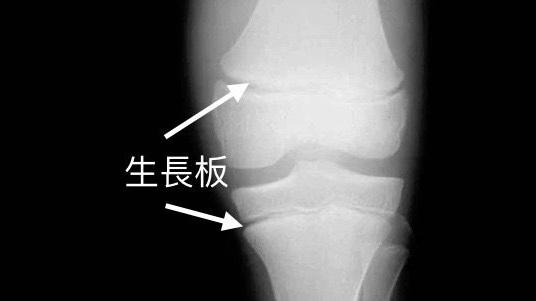

贏在生長板閉合前

至於生長板,位於長骨兩端的軟骨區,是骨骼得以延長的關鍵部位。當青春期結束,生長板便會閉合,骨骼亦不會再變長。女孩子的生長板,通常在15至16歲閉合,而男孩子則為17至18歲。要促進骨骼健康成長,便需要營養、運動量並內分泌三方面配合。每天均衡飲食,可提供骨骼生長所需的蛋白質、鈣質和維他命D。但青少年所喜愛的高糖高鹽快餐,不但令他們減少進食高鈣食物,更會影響腸道吸收鈣質,及增加鈣質從排尿中流失。雖然沒有一項運動,與增高有高度相關性,但科學研究已證實,生長板在張力下,會加速軟骨增生,使骨骼延長。故此,多做伸展拉筋運動和吊單槓,可施加張力於骨骼。至於帶氧運動(例如跳繩和跑步),亦增加血液流經生長板,並生長激素分泌,對促進骨骼生長有正面作用。